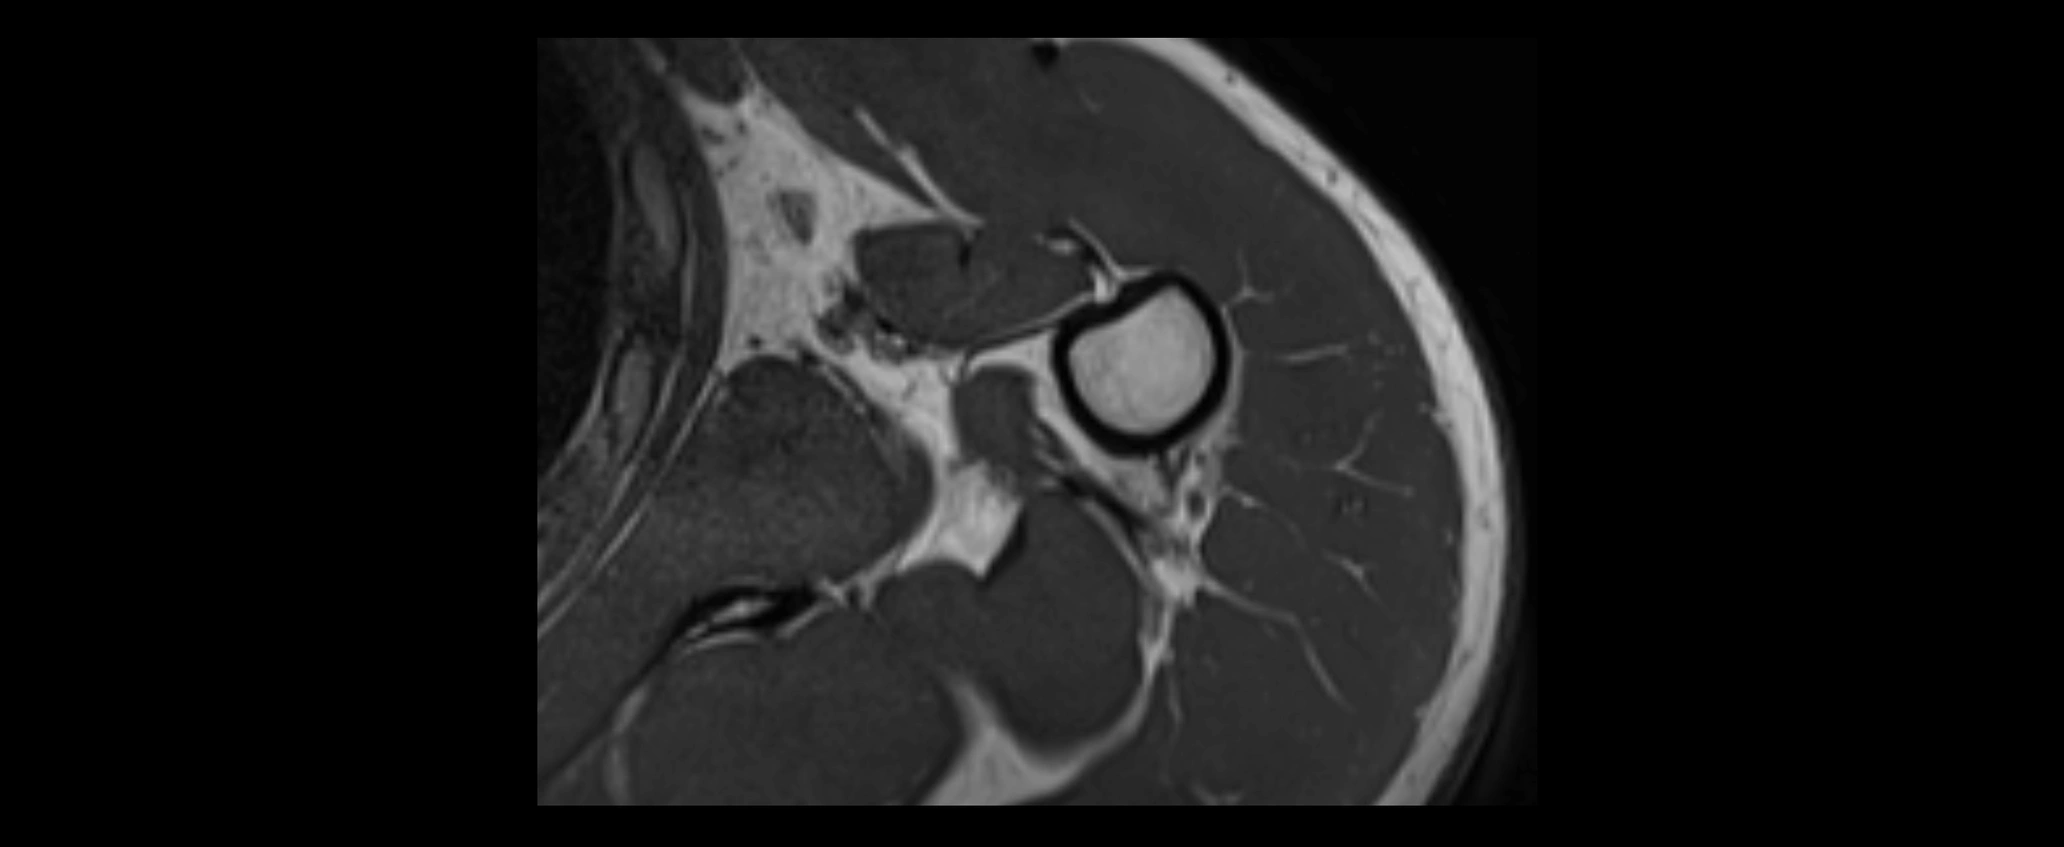

MRI images

image

CT image